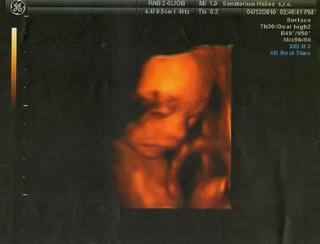

ja mam dnes po bezne gyn.kontrole,dopadla v poradku..miminko krasne vyrostlo,spinkalo a cucalo si palecek,pohlavi samozrejme neukazalo,nozky melo u sebe...tak snad budem moudrejsi ve ctvrtek na velkym UTZ....ja celou noc dneska nespala,jsem to cela ja,tesim se a zaroven se strachuji,nerviky pracuji,takze usnout je zazrak..dneska snad budu spat a ze stredy na ctvrtek mazec......dnes mi pekne lita tlak a furt se potim a mam klepavou......vcera to se mnou svihlo v zelenine,tak me ted kazdy hlida...tatka se mnou je i v koupelne....tak pekny den holky........ja jdu pracovat a vecer se za vami podivam....pa